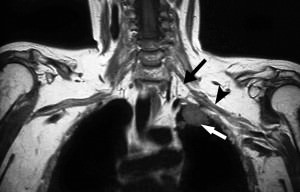

В диагностике важное место занимает анамнез с наличием провоцирующих факторов. Практически в 100% случаев курение в сочетании хотя бы с несколькими симптомами из обоих синдромов говорит об опухоли Панкоста. Подтверждением диагноза станет рентгенологическое обследование, в том числе компьютерная томография. Затем проводится бронхоскопия с забором биоптата или смыва из бронхов на предмет обнаружения атипичных клеток. Лечение сложное, и, как правило, включает в себя хирургическое вмешательство — удаление легкого или большей его части, а также кровеносных и лимфатических сосудов, нервов, ребер и, нередко, отростков позвонков. Одновременно с операцией проводят массивную химиотерапию, лучевую терапию.